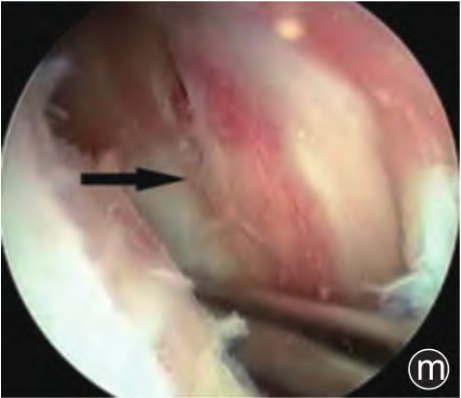

典型病例見(jiàn)圖1。

圖1 病人,男,38歲,因左膝關(guān)節(jié)腫痛、活動(dòng)受限1年,加劇1個(gè)月入院。入院診斷為“左膝關(guān)節(jié)痛風(fēng)性關(guān)節(jié)炎”,WOMAC評(píng)分:53分,Kellgren?Lawrence分級(jí):I級(jí),行左膝關(guān)節(jié)關(guān)節(jié)鏡下高頻脈沖沖洗術(shù)。

高頻脈沖無(wú)法有效清理交叉韌帶及滑膜上的痛風(fēng)石,改為刨剝刀和刮匙清理交叉韌帶(j)和滑膜(k)痛風(fēng)石

清理結(jié)束后交叉韌帶(l)和滑膜(m)組織破壞較多